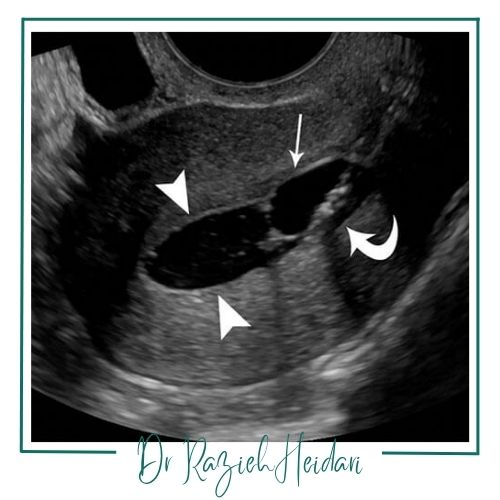

سونوهیستروگرافی (Sonohysterography) روشی ایمن و غیرتهاجمی برای بررسی حفره رحم است. در این روش با تزریق سرم نرمال سالین و استفاده از سونوگرافی ترانسواژینال، حفره رحم بهطور دقیقتر دیده میشود و مشکلاتی مانند پولیپ، فیبروئید، سپتوم یا چسبندگیهای داخل رحم قابل شناسایی هستند. برخلاف هیستروسالپنگوگرافی (HSG) که با اشعه ایکس و ماده حاجب یددار انجام میشود و برای بررسی لولههای فالوپ کاربرد دارد، سونوهیستروگرافی بیشتر بر ارزیابی داخل رحم تمرکز دارد و هیچگونه تابش اشعهای ندارد.